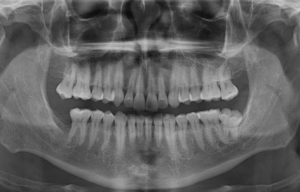

Más de 200 casos clasificados por especialidades y patologías

La cavidad del seno maxilar se subdivide comúnmente por tabiques. Los septos del seno maxilar son estructuras delgadas de hueso cortical. Estos tabiques pueden dividir